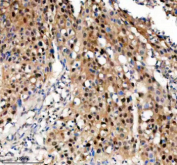

Immunohistochemical staining of TNFAIP2 using anti-TNFAIP2 antibody. TNFAIP2 was detected in a paraffin-embedded section of human bladder cancer tissue. Heat mediated antigen retrieval was performed in EDTA buffer (pH 8.0, epitope retrieval solution). The tissue section was blocked with 10% goat serum. The tissue section was then incubated with 2 ug/ml rabbit anti-TNFAIP2 antibody overnight at 4oC. Peroxidase Conjugated Goat Anti-rabbit IgG was used as secondary antibody and incubated for 30 minutes at 37oC. The tissue section was developed using an HRP secondary and DAB substrate.